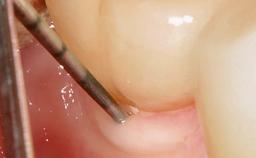

A 79-year-old female patient was referred to the Department of Periodontology of the University of Bern, Switzerland by her private dentist in May 2019. She had been rehabilitated in May 2005 with two tissue-level implants (Institut Straumann AG, Basel Switzerland) at sites 13 and 15, supporting a three-unit cemented fixed dental prosthesis (FDP). The metal-ceramic FDP had been cemented permanently with a glass-ionomer cement (Ketac Cem; 3M ESPE, Seefeld, Germany). Implant 13 had been diagnosed with peri-implant mucositis by the referring dentist in the course of regular supportive therapy. The patient was in good general health, did not smoke, and exhibited good self-performed plaque control.